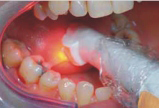

FotoSan 360

Přístroj na principu světlem aktivovaná desinfekce neboli fotodynamická antimikrobiální chemoterapie. Přístroj s okamžitým účinkem ničí veškeré mikroorganismy bez jakýchkoli vedlejších účinků. Jedná se o bezbolestné ošetření, které nevyžaduje anestezii, nemá vedlejší účinky a ničí 99% bakterií. Používá se především v parodontologii a implantologii při léčbě zánětů v okolí zubů a implantátů (dezinfekce tzv. chobotů), záchovné stomatologii (ošetření kazů) i endodoncii (dezinfekce kanálků zubu).